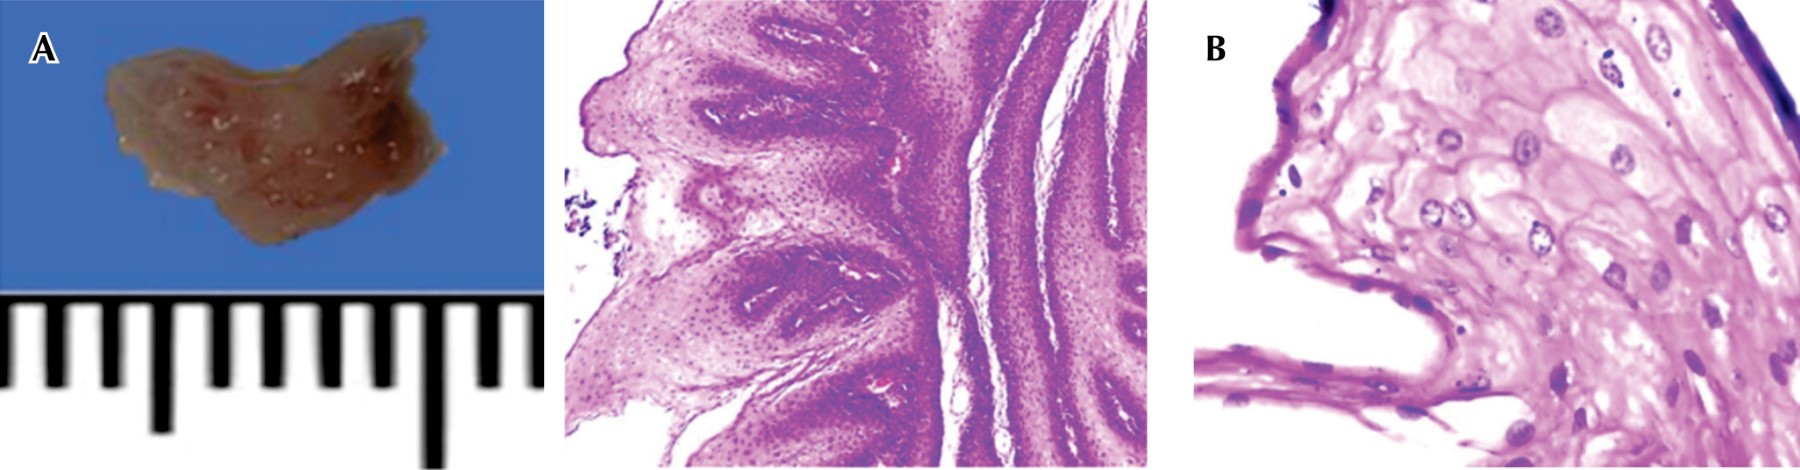

Se programa tiempo quirúrgico para la toma de biopsia, posterior a ello se obtiene los siguientes resultados del histopatológico: a nivel microscópico se observa fragmento de tejido de forma irregular de 0.5 × 0.3 × 0.2 cm de dimensiones mayores. Presenta superficie externa irregular con áreas de apariencia papilar, color rosa con café claro y despulida. La superficie de corte es sólida, café claro y homogénea. Es de consistencia blanda. A nivel macroscópico se observa lesión verrugosa conformada por proyecciones papilares irregulares, presenta paraqueratosis, papilomatosis y zonas con acantosis. Los queratinocitos proliferantes son poligonales, cohesivos. El citoplasma es amplio, eosinófilo de bordes bien delimitados, conservan la polaridad y maduración celular. Los núcleos son redondos de cromatina granular fina. No se aprecia nucléolos aparentes. No hay evidencia de mitosis ni pleomorfismo, el tejido conectivo subepitelial se observa escaso infiltrado inflamatorio de predominio linfocítico y vasos sanguíneos conectivos (Figura 2).

Figura 2